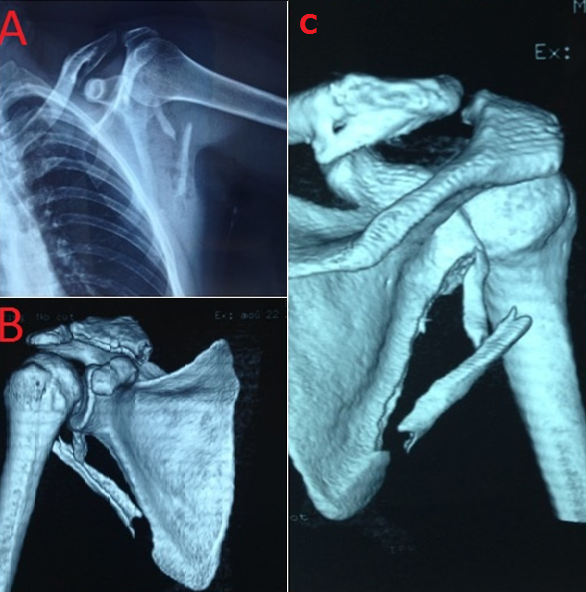

Scapular fractures are considered a very unusual injury, among studies in adults they account for 1-3% of all fractures, and 5% of fractures involving the shoulder, because the anatomic location and the soft tissues protect the scapula. Consequently, they are usually caused by high-energy vesicular trauma or by falling from a height.Conservative treatment commonly produces good or excellent results.We report a very rare case of a fracture of the lateral border of the scapula associated with lesion of the brachial plexus. A 38-year-old man injured his left shoulder in a traffic accident.In his physical examination, there was a deficit partial nervous of the brachial plexus. The X-ray examination revealed a displaced fracture of the lateral border of the scapula.A computed tomography scan with 3D reconstruction confirmed the diagnosis. Electromyographicexamination two weeks after the injury showed a compression of the brachial plexus. The fracture was treated conservatively. By 4 months after the injury there was further improvement in both sensory and motor function, and by 8 months there was sensation in the autonomous zones of both median and ulnar nerves and good return of muscle power.